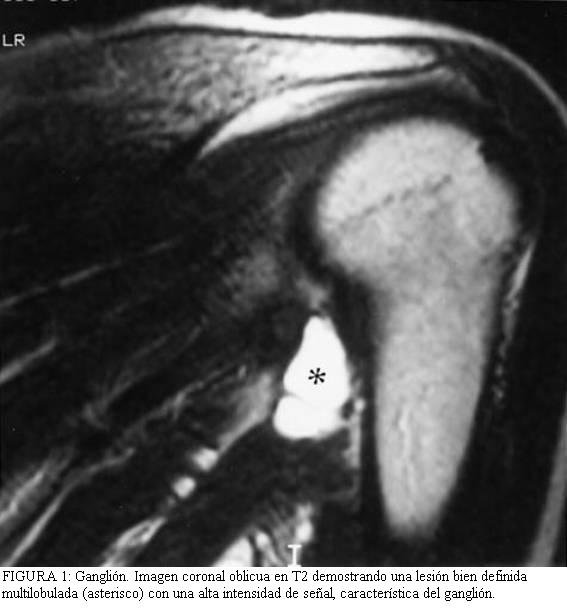

Los

2 y 3) son